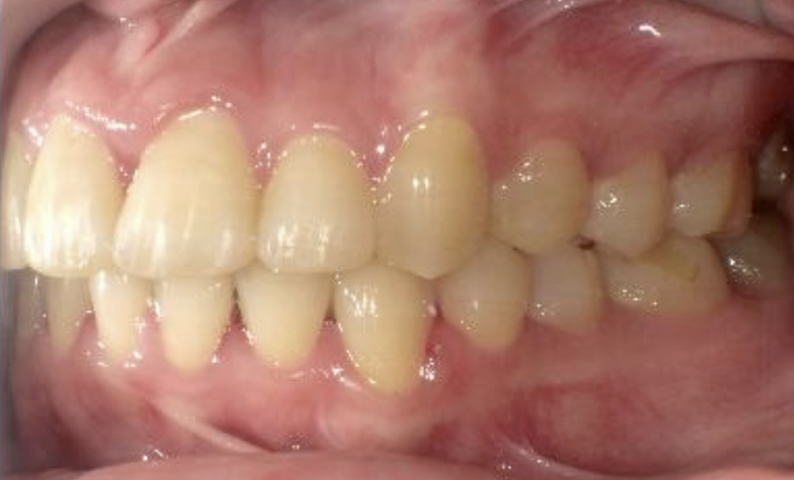

症例_025 上下顎の部分矯正

治療期間:13ヶ月金額:51万円+税女性前歯のガタガタ出っ歯

| Before | After |

|---|---|